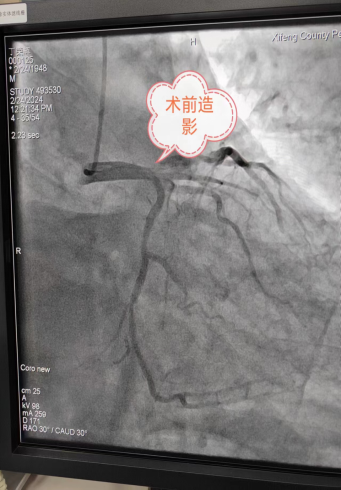

11时54分患者到达导管室,12时10分开始穿刺,12时17分造影开始,12时45分导丝通过,14时16分患者手术完成。

手术前血管